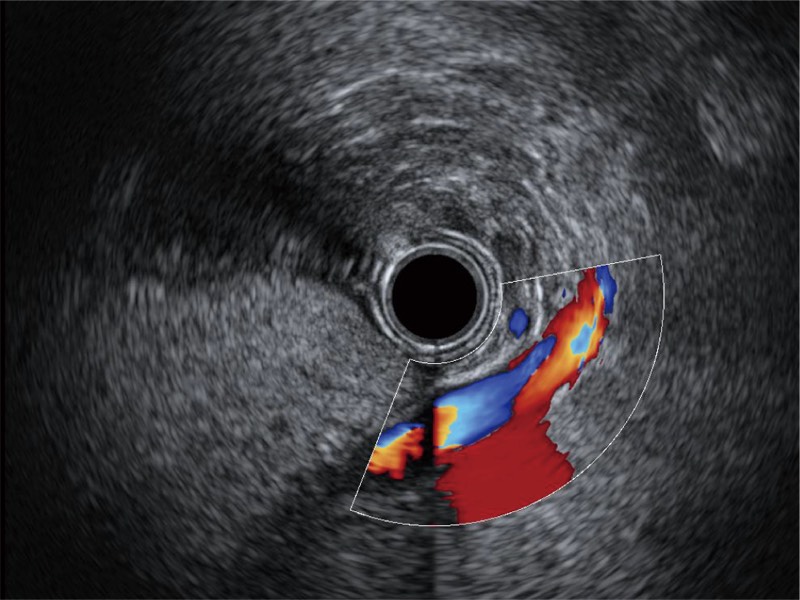

• 食管内间质瘤清晰显像